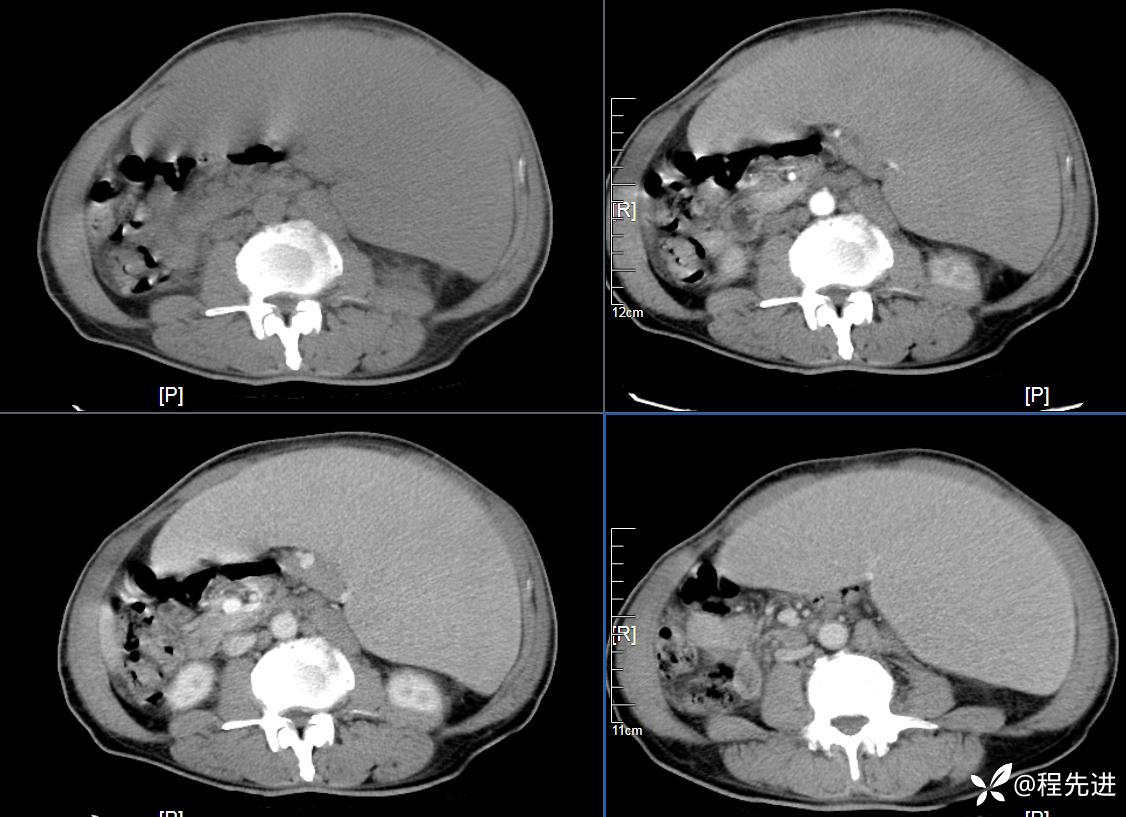

CT平扫及增强3期: